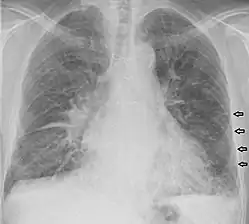

Kerley lines

Kerley lines are a sign seen on chest radiographs with interstitial pulmonary edema. They are thin linear pulmonary opacities caused by fluid or cellular infiltration into the interstitium of the lungs. They are named after Irish neurologist and radiologist Peter Kerley.[1][2]

Kerley B lines

These are short parallel lines at the lung periphery. These lines represent interlobular septa, which are usually less than 1 cm in length and parallel to one another at right angles to the pleura. They are located peripherally in contact with the pleura, but are generally absent along fissural surfaces. They may be seen in any zone but are most frequently observed at the lung bases at the costophrenic angles on the PA radiograph, and in the substernal region on lateral radiographs.[3] Causes of Kerley B lines include pulmonary edema, lymphangitis carcinomatosa and malignant lymphoma, viral and mycoplasmal pneumonia, interstitial pulmonary fibrosis, pneumoconiosis, and sarcoidosis. They can be an evanescent sign on the chest x-ray of a patient in and out of heart failure.